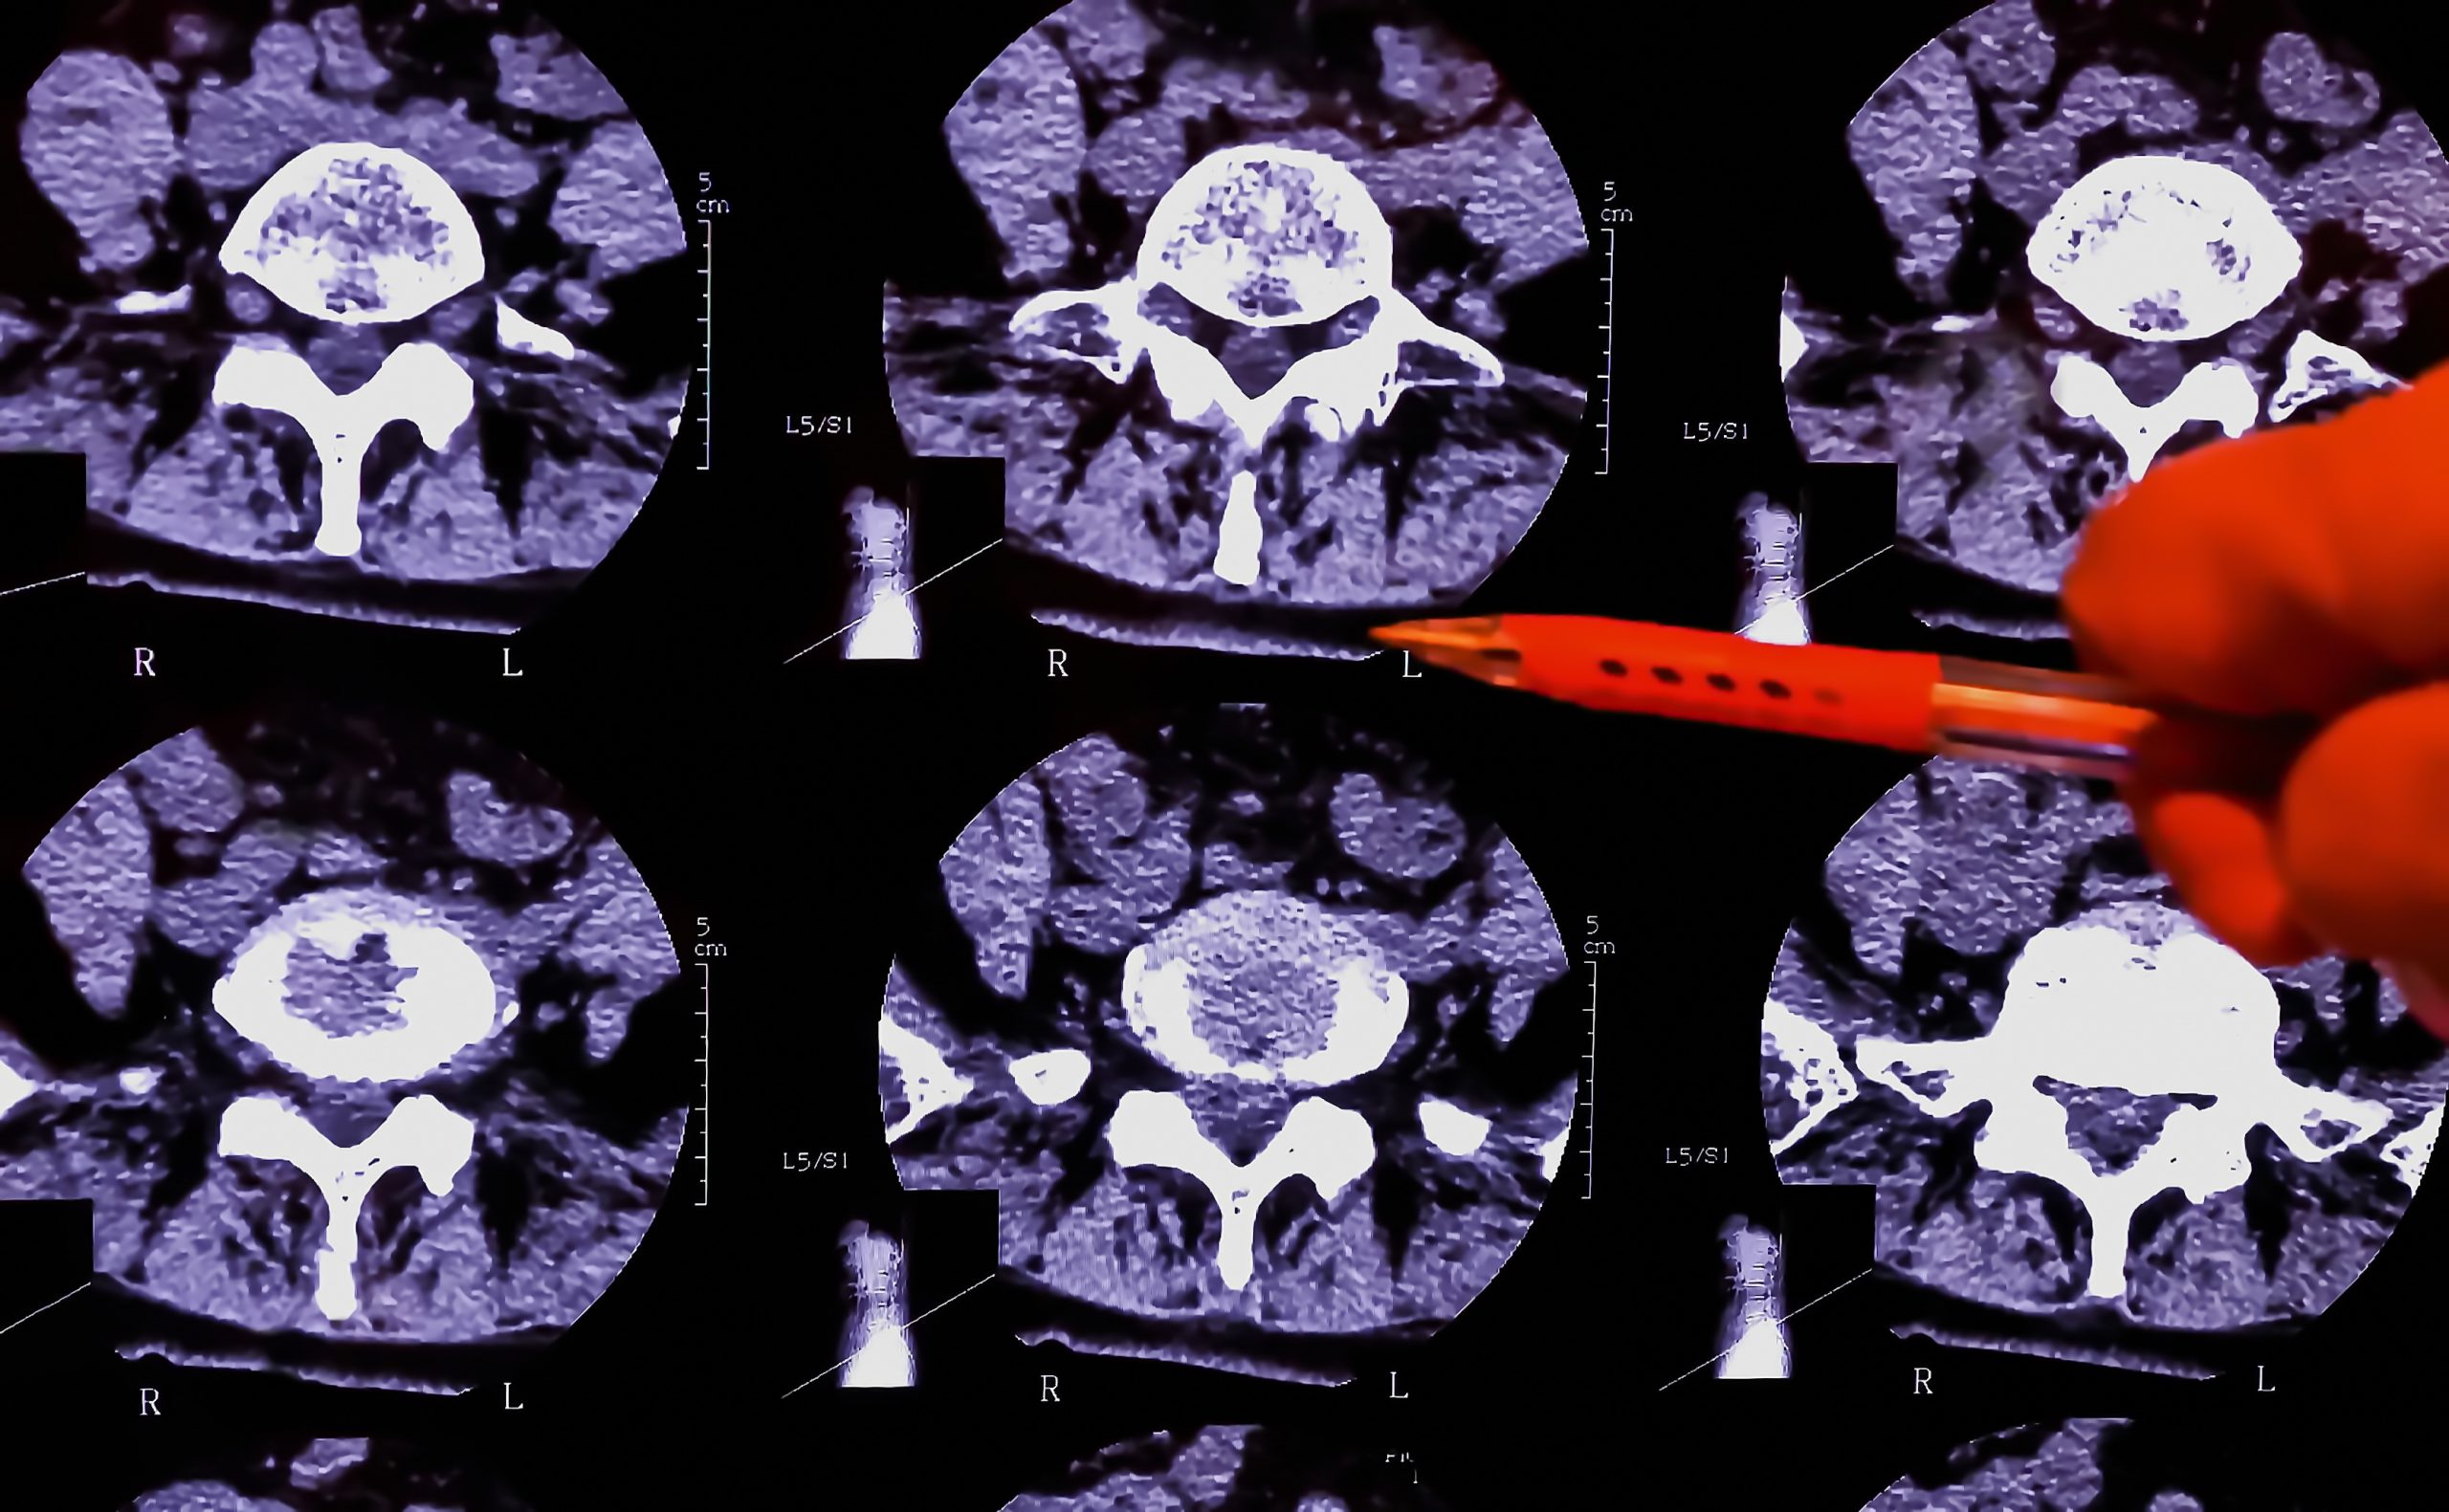

Ein Blick ins Innere des menschlichen Körpers – heute für Ärzte selbstverständlich, technisch jedoch eine Höchstleistung. Die Computertomographie (kurz CT) zählt zu den fortschrittlichsten bildgebenden Verfahren der modernen Medizin. Sie liefert hochauflösende Bilder von Organen, Geweben und Strukturen, ganz ohne schädliche Strahlung. Ob in der Neurologie, Orthopädie oder Onkologie: Die Computertomographie ist aus dem medizinischen Alltag nicht mehr wegzudenken.

CT-Geräte stellen außergewöhnlich hohe Anforderungen an alle verbauten Komponenten. Antriebssysteme müssen nicht nur absolut zuverlässig und langlebig sein, sondern auch unter besonderen physikalischen Bedingungen präzise funktionieren. Genau hier kommen spezialisierte Lösungen wie Ringmotoren und Segmentmotoren ins Spiel.